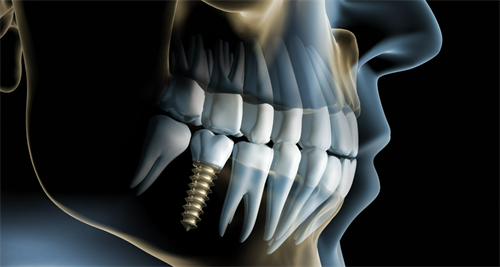

其中,种植牙技术采用的是新型的数字化导板即刻种植技术,可以让医生更正确地掌握种植牙的位置和方向,大大缩短了顾客的复诊时间,对于半口和全口种植牙手术也是一种修复结果较好的技术。